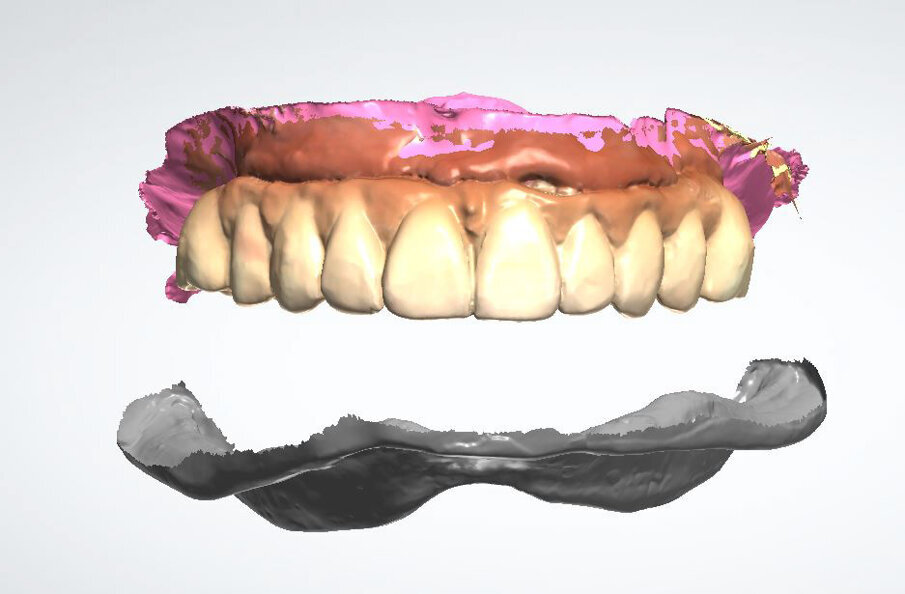

Fig. 4_Scansione intraorale superiore e inferiore.

Fig. 6_La protesi superiore e inferiore disegnate con le librerie Ivoclar Ivotion.